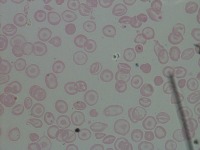

Medical Diagnosis and Research: The "New-Chula" model could be used in medical laboratories and hospitals to automatically identify and classify different cell types in blood samples. This could assist in diagnosing various blood disorders or diseases such as anemia or leukemia, thereby speeding up analysis and treatment processes.

Education and Training: The model could serve as an educational tool for medical students or professionals in training. By using this model, they could learn to identify various types of cells more quickly and accurately, enhancing their understanding of hematology.

Pharmaceutical Trials: During drug testing and development, pharmaceutical companies may use this model to analyze the impact of drugs on different cell types in order to assess effectiveness or side effects.

Public Health Monitoring: Governments and public health organizations could use it to monitor the health condition of the general population, potentially detecting the early stages of an outbreak or epidemic.

Biotechnology Industry: Biotech firms or research labs may use this model for particular research projects involving genetic modification or cellular biology studies where identification and classification of different cell types is necessary.